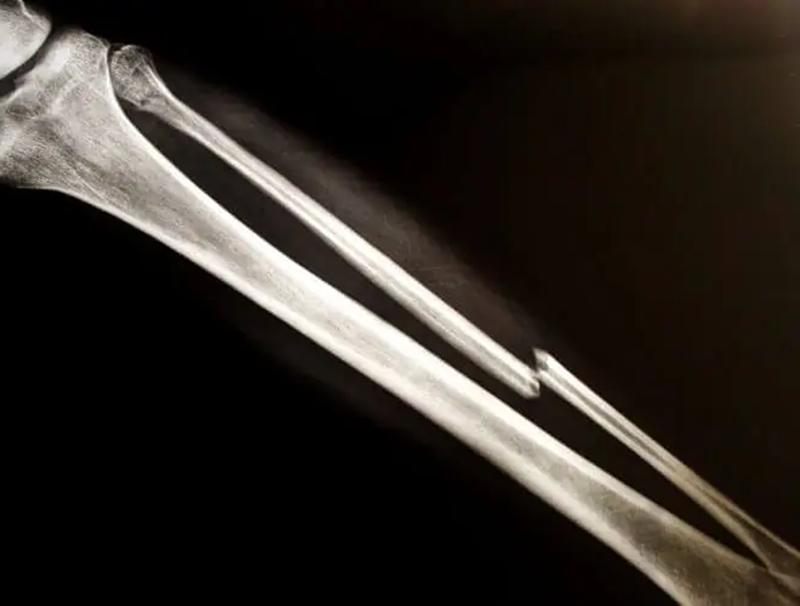

大部分骨折都会在三个月左右愈合,先出现血肿和炎症反应,死亡的细胞会被清除。再往后进入修复阶段,骨折的地方出现骨骼和纤维组织的新细胞,形成被称作骨痂的橡胶状组织。接下来骨痂越来越硬,硬度可能超过正常的骨头,一般三个月左右骨折部位已经比较坚固的长在一起,关节或者肢体的功能也基本已经恢复。这时候叫临床愈合,患者可以正常活动。但完全康复需要一年左右,骨痂被新骨代替,这叫做骨性愈合。